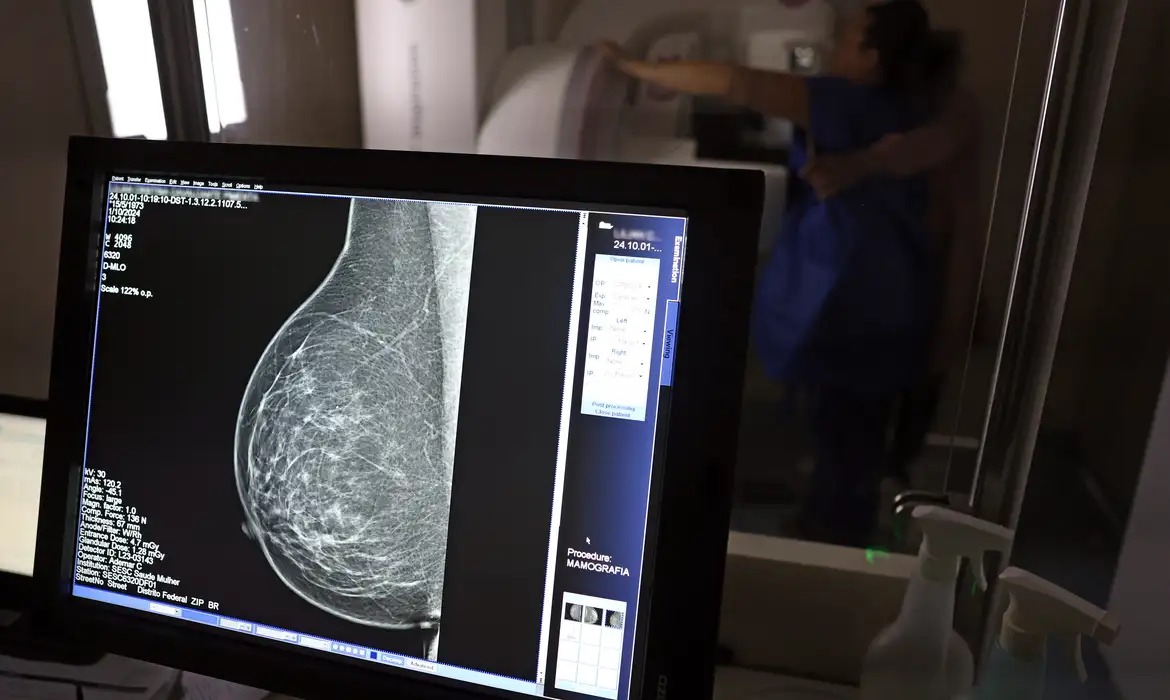

Mamografia agora é recomendada a partir dos 40 anos

Faixa de 40 a 49 anos concentra 23% dos casos de câncer de mama

O Ministério da Saúde passou a recomendar o acesso a mamografia, via Sistema Único de Saúde (SUS), para mulheres de 40 a 49 anos – mesmo que não haja sinais ou sintomas de câncer de mama. De acordo com a pasta, a faixa etária concentra 23% dos casos da doença, e a detecção precoce aumenta as chances de cura.

Foto: José Cruz/Agência Brasil“A paciente deve ser orientada sobre os benefícios e desvantagens de fazer o rastreamento. Mulheres nesta idade tinham dificuldade com o exame na rede pública de saúde por conta da avaliação de histórico familiar ou necessidade de já apresentar sintomas”, informou o ministério em nota.